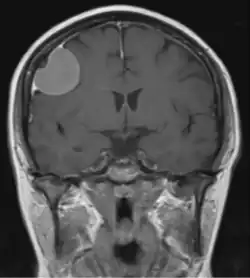

Dural tail sign

The dural tail sign (also known as dural thickening, the flare sign, or the meningeal sign) is a radiological finding observed in magnetic resonance imaging (MRI) studies of the brain that refers to a thickening of the dura mater immediately adjacent to a mass lesion, such as a brain tumor.[1] Initially, the dural tail sign was thought to be pathognomonic of meningioma, a slow-growing tumor that arises from the meninges.[1] However, subsequent studies have shown that it can also be observed in various intra- and extra-cranial pathologies and in spinal lesions.[1] It is not a completely sensitive finding, as it is seen in only 60-72% of cases.[2] It is not completely specific either, as it has been described associated with lesions like neuromas, chloromas, pituitary diseases, granulomatous disorders, cerebral Erdheim-Chester disease, lymphomas, metastasis, hemangiopericytomas, schwannomas, and gliomas such as glioblastoma multiforme (GBM).[2][3] The final diagnosis should be further established through cerebrospinal fluid analysis or histopathological examination following a biopsy.[3]